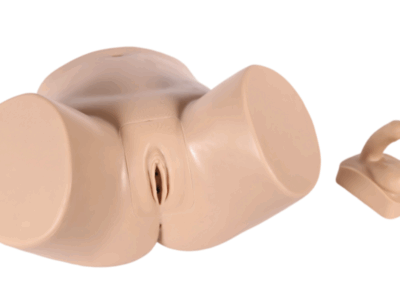

Modelos

Anatômicos

Ferramentas para estudo detalhado do corpo humano.